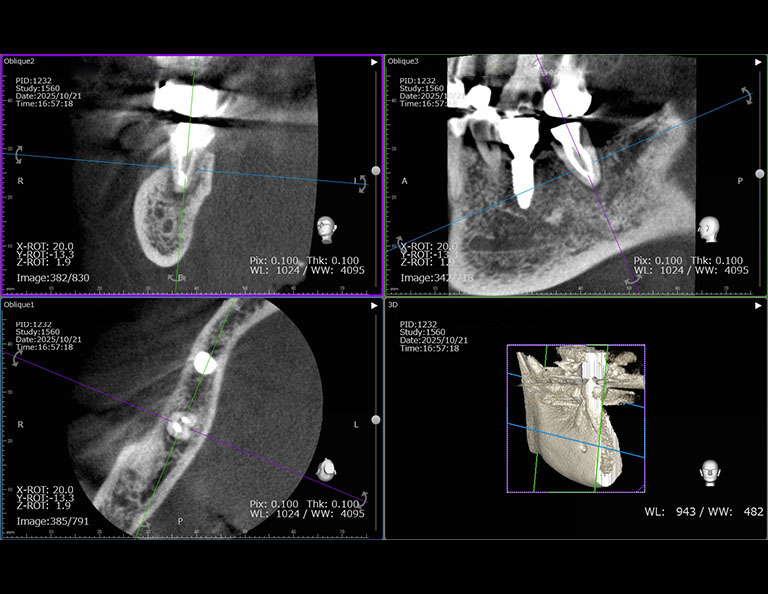

術前のCTです。

歯根の周囲の骨吸収が認められます。

根管治療後のCTです。

歯根の周囲の骨吸収もだいぶ改善されました。